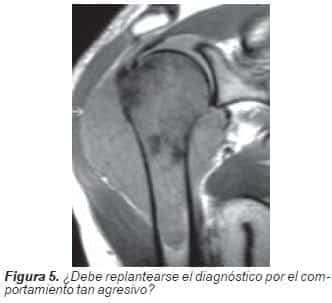

La Resonancia nuclear magnetica: evidencia una lesión tumoral con masa de tejidos blandos, de origen medular, que se extiende hasta el borde inferior de la glenoides, levanta el deltoides, y se insinúa en el hueco axilar, respetando aparentemente los vasos y el plejo braquial.

Condrosarcoma dediferenciado a un sarcoma de alto grado (osteosarcoma).